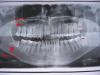

Dkristof Опубликовано 27 июня, 2011 Поделиться Опубликовано 27 июня, 2011 Сходил к врачу по поводу выпирающих вперед троек. Думал что вперед они "вылезли" из-за восьмерок. Врач же говорит что далеко не факт что в этом виноваты верхние восьмерки и что удалять их пока не надо. Но мне все равно боизно, а ну как верхние зубы продолжат лезть вперед. Так же после рентгена выяснилась ещё одна проблема. Нижняя восьмерка вообще лежит горизонтально. И вот её то, как сказал врач, надо удалять обязательно. Говорит что зуб открытый и рано или поздно появится кариес и он начнет беспокоить. Но операция сложная и дорогая, да и страшно. Вопросы:1) Что посоветуете по верхней челюсти? Надо удалять зубы мудрости или не надо? Если их не трогать, остальные зубы "гармошкой" не пойдут? Наподобие троек? Да и положение самих троек не усугубится? 2) Что скажите по поводу нижней челюсти? Восьмерку и правда нужно удалять? 3) Подобная операция и правда стоит 9к руб или у меня просто клиника дорогая? В общем жду советов и мнений специалистов. Ссылка на комментарий

Dkristof Опубликовано 15 августа, 2011 Автор Поделиться Опубликовано 15 августа, 2011 (изменено) Сейчас удалил две восьмерки. Нижнюю и верхнюю справа (ну на снимке это право, а у меня слева). А вот горизонтально-растущую нижнюю восьмерку слева реши оставить на потом, но её тоже удалять в любом случае. После того как эта парочка заживет. А вот стоит ли удалять оставшуюся верхнюю восьмерку я не уверен, она же уже вылезла. И не будет толкать остальные зубы. или все же будет? Чем она может навредить? Изменено 15 августа, 2011 пользователем Dkristof Ссылка на комментарий